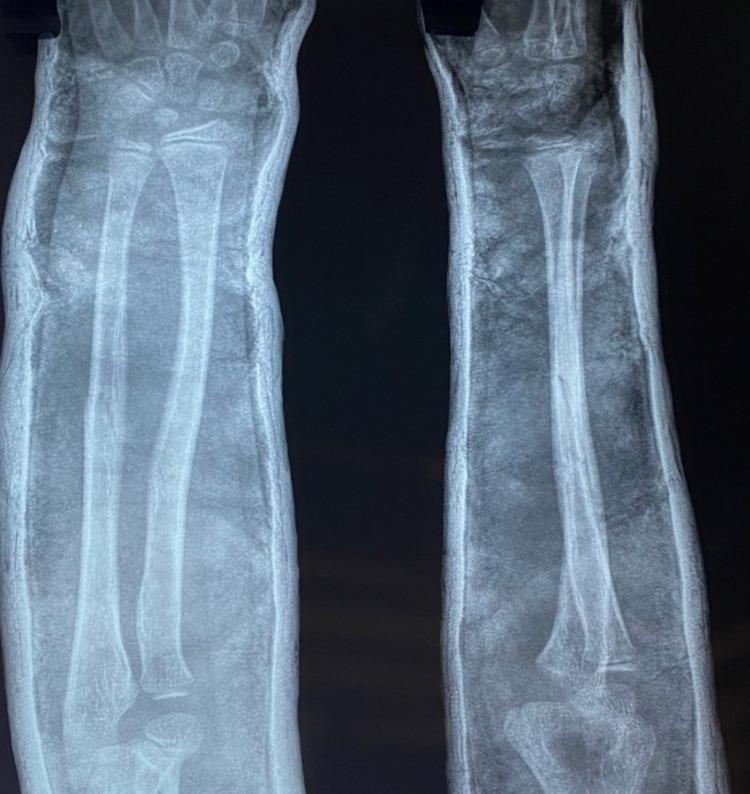

Introduction Fractures in children are extremely common scenarios encountered by orthopedicians. Conservative treatment has been the most preferred choice for the management of diaphyseal forearm fractures. Traditionally, pediatric forearm fractures are treated by above elbow plaster cast with the elbow flexed to 90 degrees. The purpose of this study was to evaluate the functional and radiological outcomes of children treated with closed reduction and extension casting for forearm fractures. Patient and methods This is a prospective study evaluating the functional and radiological outcomes of 30 children of less than the age of 14 years and without pathological fractures, treated with closed reduction and extension casting for forearm fractures, either both radius and ulna or radius or ulna at middle third level, who reported to the Department of Orthopedics, Dr. D.Y. Patil Medical College, Hospital, and Research Center, Pune, India, between September 2019 and March 2022. Results The mean pre-operative angulation in radius (antero-posterior {AP}) was 22.7, radius (lateral {LAT}) was 24.2, ulna (AP) was 31.2, and ulna (LAT) was 29.2. The immediate post-operative angulation of radius (AP) was 0.7, radius (LAT) was 3.2, ulna (AP) was 0.6, and ulna (LAT) was 4.9. Cast status at two weeks, 83.3% had intact cast and 16.7% had loosened casts. Post removal, most patients had a good rotation of motion (ROM) at three and six weeks. Conclusion Casting with extended elbow is much better as compared to flexion casting in the hands of a trainee doctor. Furthermore, chances of loss of reduction are negligible in extension casting as compared to flexion casting.

引言 儿童骨折是骨科医生经常遇到的极为常见的情况。保守治疗一直是治疗肱骨干骨折的最首选方法。传统上,小儿前臂骨折采用屈肘90度的上臂石膏固定治疗。本研究的目的是评估采用闭合复位和伸直位石膏固定治疗前臂骨折的儿童的功能和影像学结果。

患者与方法 这是一项前瞻性研究,评估了2019年9月至2022年3月期间,在印度浦那D.Y.帕蒂尔医学院、医院和研究中心骨科就诊的30名14岁以下且无病理性骨折的儿童的功能和影像学结果,这些儿童因前臂骨折接受了闭合复位和伸直位石膏固定治疗,骨折部位为桡骨和尺骨或桡骨或尺骨的中三分之一段。

结果 桡骨术前平均成角(前后位{AP})为22.7,桡骨(侧位{LAT})为24.2,尺骨(AP)为31.2,尺骨(LAT)为29.2。术后即刻桡骨(AP)成角为0.7,桡骨(LAT)为3.2,尺骨(AP)为0.6,尺骨(LAT)为4.9。两周时石膏情况,83.3%的石膏完整,16.7%的石膏松动。拆除石膏后,大多数患者在三周和六周时运动范围(ROM)良好。

结论 对于实习医生来说,伸直位石膏固定比屈曲位石膏固定要好得多。此外,与屈曲位石膏固定相比,伸直位石膏固定复位丢失的几率可以忽略不计。